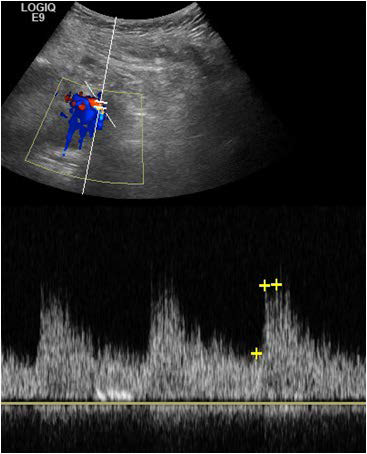

Figure 6: Doppler Ultrasound showed normal waveforms of renal parenchyma.

figure 6